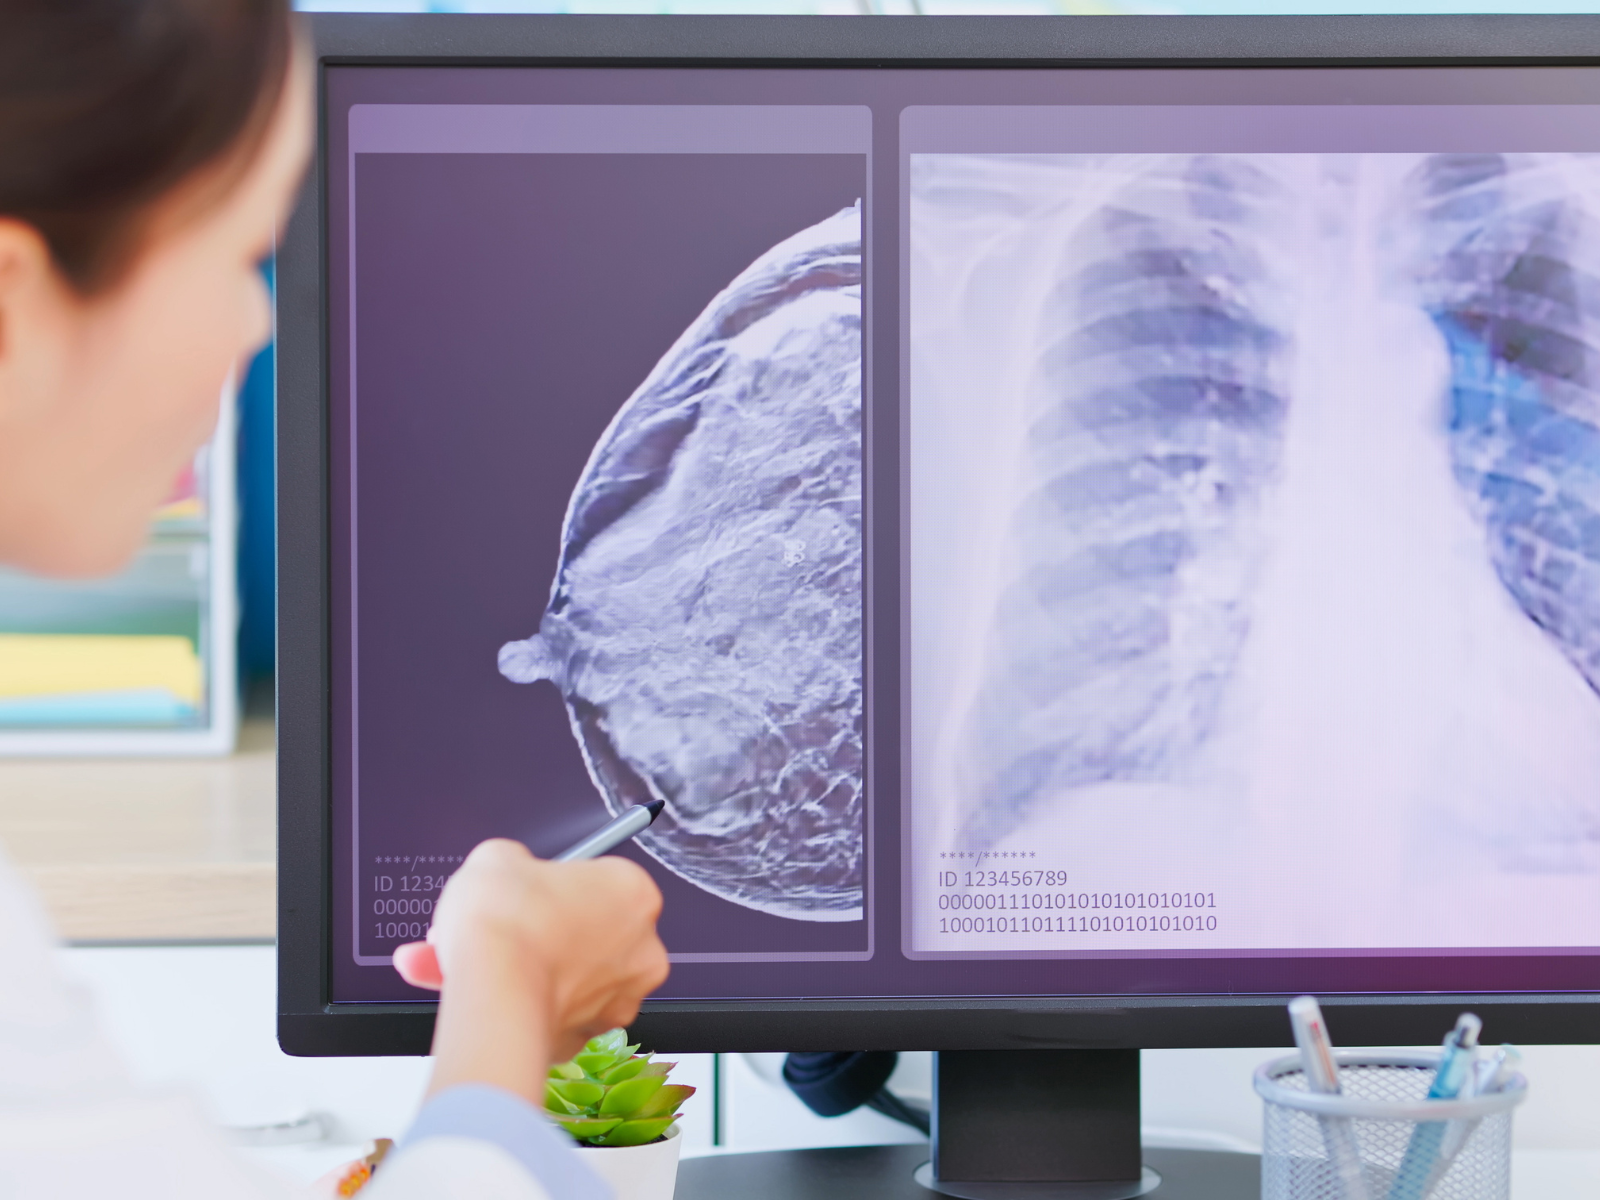

سرطان پستان زمانی رخ می دهد که سلول های غیرطبیعی در بافت پستان شروع به رشد و تکثیر کنترل نشده می کنند. این بیماری می تواند به صورت توده، تغییرات پوستی یا ترشحات غیرطبیعی بروز کند و در صورت تشخیص زودهنگام به خوبی قابل درمان است.

سرطان پستان یکی از رایجترین انواع سرطان در زنان است و با رشد غیرطبیعی سلولها در بافت پستان مشخص میشود. این بیماری میتواند در یک یا هر ...